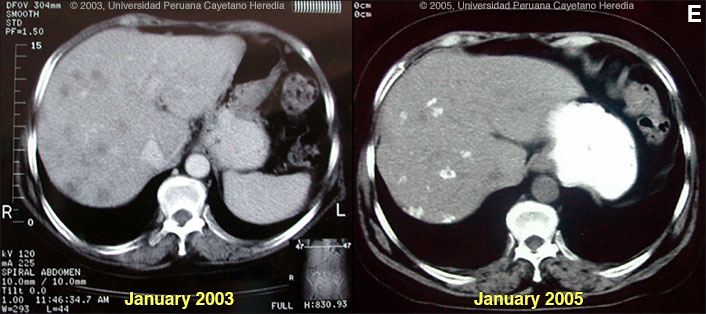

![]() Discussion: Further examination of omental tissue taken at the original surgery showed larvae of F. hepatica [Image C]. IgG FAS2 ELISA [Trans R Soc Trop Med Hyg. 1999 Jan-Feb;93(1):54-7] was positive for Fasciola hepatica at 3.2 OD units (Normal <0.2). Fasciola hepatica is a trematode (fluke or flatworm) in which the mature adult parasites inhabit the large biliary ducts. The adults are from 1 to 3 cm long and attach to the biliary epithelium by a single ventral sucker [Image D from our case files shows an endoscopic view of an adult in the common bile duct]. In the absence of direct visualization, characteristic eggs can be seen on stool examination, but more often patients present in the early migratory phases of infection prior to maturation of the worm and the onset of egg-laying. Specific serology is test of choice. As with all other trematodes, Fasciola hepatica requires a snail intermediate host. Eggs produced by the hermaphroditic adults pass with the feces and hatch, releasing larvae in fresh water. After passing through a snail, mature cercariae emerge and rapidly encyst on various kinds of aquatic vegetation such as watercress. After ingestion by a human or animal definitive host, the metacercariae excyst in the duodenum and larvae pentetrate the intestinal wall and subsequently migrate directly into the liver via Glisson's capsule. The larvae then embark on a destructive migratory process through the hepatic parenchyma for 3 to 4 months until they reach large biliary ducts where they mature to adults. The distribution of Fasciola hepatica is cosmopolitan, but is by far the most common in sheep-raising areas where herbivores are common definitive hosts. Heavily infected sheep develop "sheep liver rot". Other important definitive hosts are goats, cattle, horses, llamas, vicunas, and camels. The contiguous altiplano regions of the Peruvian and Bolivian Andes are highly endemic, with human prevalence rates of as high as 67% in some villages. Egypt, Cuba, and Northern Iran are also highly endemic. Cooking, which would kill the metacercariae, dramatically changes the flavor of watercress and the population is reluctant to adopt this simple measure. Our patient regularly ingested watercress. Clinically, the disease can be divided into acute and chronic phases. During the acute phase, migrating parenchymal larvae cause fever, eosinophilia, right upper quadrant pain and especially significant anorexia. Vomiting and weight loss of 20 kg or more may develop, which usually abates when the larvae mature to adults. The adult flukes in the biliary tree are generally asymptomatic but some patients develop chronic manifestations including right upper quadrant pain, nausea, vomiting, and hepatomegaly. Eosinophilia and abnormal liver function may develop but are less common than with acute disease. Adult flukes may cause hyperplasia, desquamation, thickening, and dilatation of the bile ducts. Malignant degeneration and cholangiocarcinoma such as results from chronic infection with the oriental liver fluke Clonorchis sinensis has not been reported with Fasciola hepatica. The differential diagnosis of hypereosinophilia with accompanying destructive hepatic lesions is limited. Toxocariasis causes hypereosinophilia with hepatomegaly but the pathology results from small granulomas around individual non-migrating larvae and not the large destructive tracks as was seen on the CT in our patient. Fasciola hepatica is the only trematode infection for which praziquantel is not the drug of choice. WHO has put the veterinary anthelmintic triclabendazole (Novartis) on its essential drugs list and has declared it the drug of choice despite the fact that human preparations are registered in only 2 countries. In Perú, the veterinary preparation is readily available and used. In the U.S. and many other countries the veterinary preparation can be obtained by special release from the manufacturer. The usual dosage is 10 mg/kg with a meal. Many practitioners repeat the dosage 12 to 24 hours later. In our institute the cure rate is 96% (A. Terashima, unpublished). Our patient was treated with a single 2-day cycle of triclabendazole 10 mg/kg/day with symptomatic improvement and no fever 2 weeks after treatment. WBC at follow-up was 7,800 with 20% eosinophils. Follow-up to Gorgas Case of the Week 2003-12 Only case reports but no series of sequential CT scans of the acute phase of fascioliasis have been published. Lesions are irregular, hypodense, sometimes oblong and branching. One recent published case shows serial CT scans over a 9-month period demonstrating changes in position, and shape of lesions over time, as would be consistent with the destructive nature of the migrating flukes [N Engl J Med. 2002 Apr 18;346(16):1232-9]. In a case seen by Gorgas participants in 2003 [Gorgas Case 2003-12] we demonstrated that in a case of massive fascioliasis, the destructive inflammatory tracks made by migrating larvae persist radiologically and histologically for months even after apparent parasitic cure. We have recently seen this patient in follow-up 2 years later and now report hepatic calcification as a sequelae of acute fascioliasis [Image E]. In addition, hepatic transaminases, alkaline phosphatase and bilirubin have been normal for the past 1 year, stool O & P remains negative, and the patient is asymptomatic. However, an eosinophilia of 8% persists.